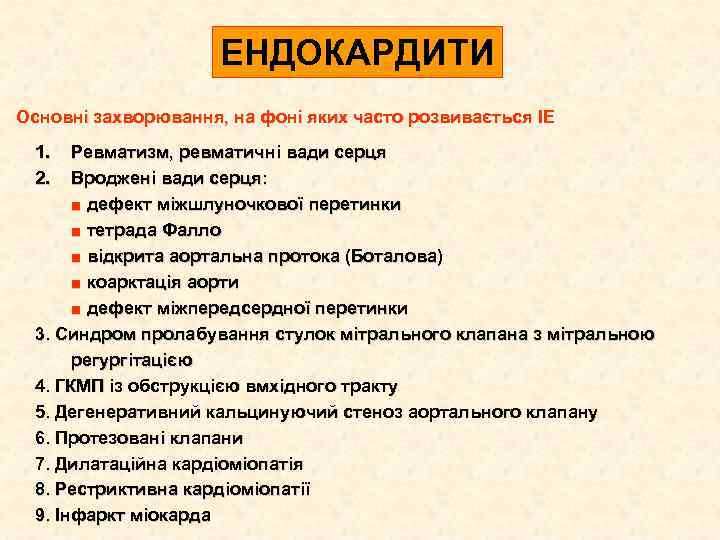

ЕНДОКАРДИТИ Основні захворювання, на фоні яких часто розвивається ІЕ 1. 2. Ревматизм, ревматичні вади серця Вроджені вади серця: ■ дефект міжшлуночкової перетинки ■ тетрада Фалло ■ відкрита аортальна протока (Боталова) ■ коарктація аорти ■ дефект міжпередсердної перетинки 3. Синдром пролабування стулок мітрального клапана з мітральною регургітацією 4. ГКМП із обструкцією вмхідного тракту 5. Дегенеративний кальцинуючий стеноз аортального клапану 6. Протезовані клапани 7. Дилатаційна кардіоміопатія 8. Рестриктивна кардіоміопатії 9. Інфаркт міокарда